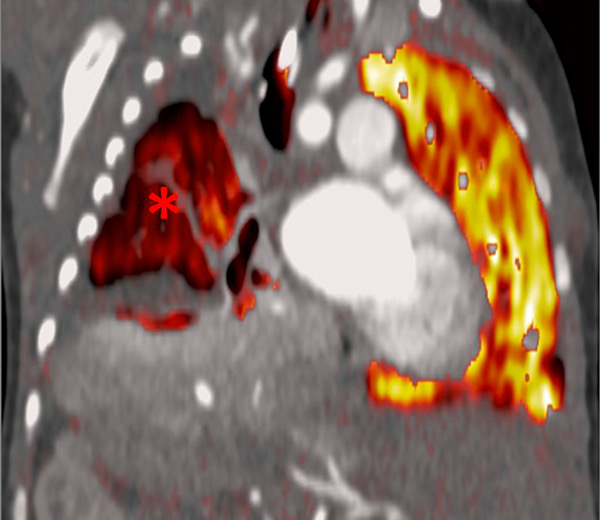

Figure 8

Eisenmenger’s syndrome secondary to a large ventricular septal defect. No vascular abnormalities were seen (A) but some ground-glass opacities (arrow) (B) with the absence of perfusion corresponded to vascular ground-glass opacities surrounded by clear heterogeneous pulmonary perfusion (C).